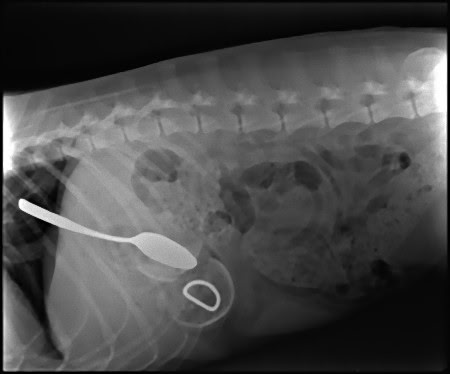

この画像を大きなサイズで見るエスキモー犬、スプーンと?

この画像を大きなサイズで見る